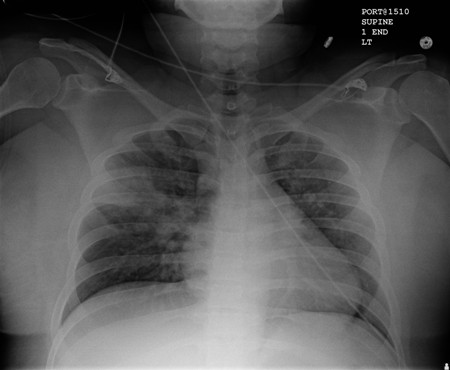

- radiografia torácica